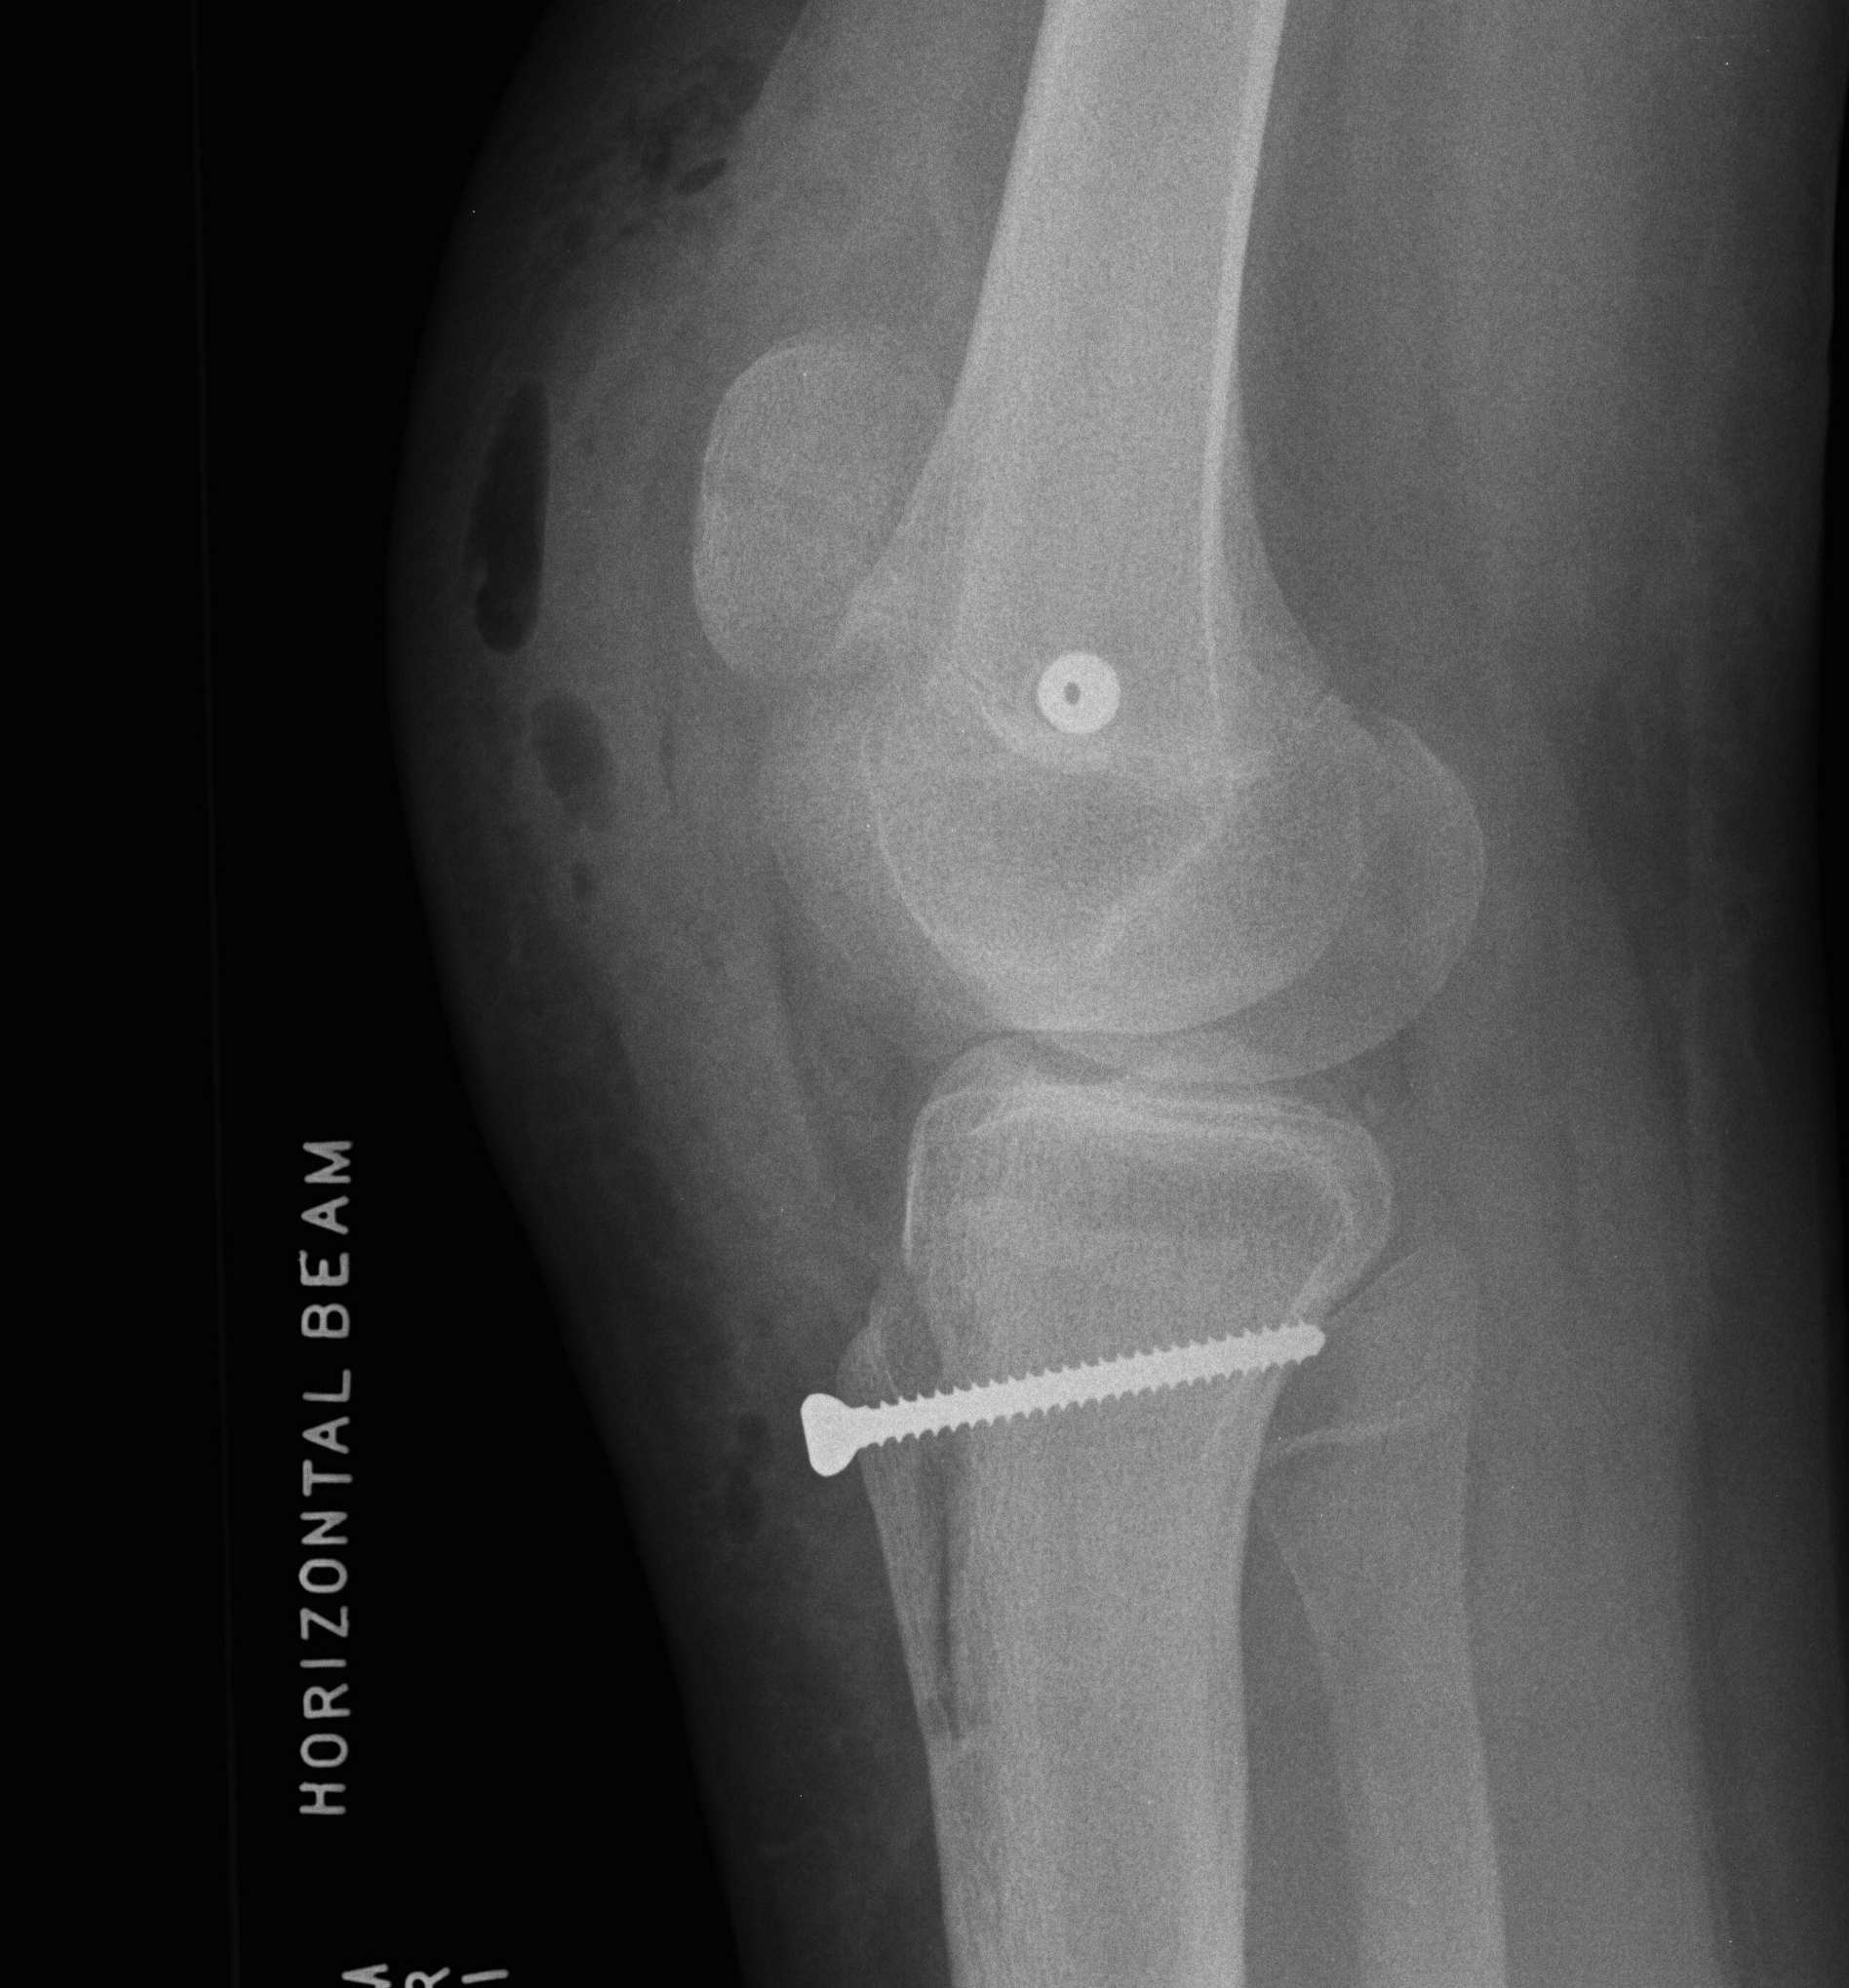

Fat Pad Syndrome

Definition

Hoffa's syndrome

- impingement of the fat pad with knee ROM

Diagnosis

Hoffa's sign

- apply pressure to fat pad each side of patella tendon with knee in flexion

- extend knee